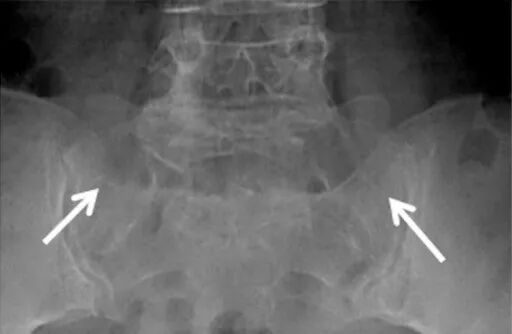

IV型:右侧LSTV II型(长箭头),左侧为III型(短箭头)

如果是正位X线平片,如果不采用特殊体位,恐怕价值不大,因为腰5横突会和骶骨嵴重叠在一起导致观察不清;在常规正位片基础上倾斜30°拍摄(AP radiograph with a 30°cranial angulation),称之为弗格森(Ferguson)射线片,此体位能够清楚显示腰5横突,是国外诊断Bertolotti综合征的首选检查方法。

(白箭指向假关节,但很难清晰显示)